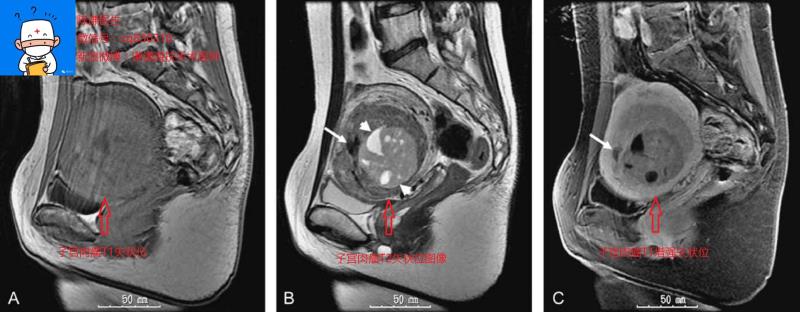

首先我们看看正常的子宫肌瘤超声和磁共振图像

1、子宫肌瘤VS子宫腺肌瘤:单独看这两个名字其实就已经有点乱了,再加上有时候症状表现也基本相似,就更不容易区别了。子宫腺肌瘤属于子宫腺肌症的一种特殊类型;大多数的子宫腺肌症病灶都比较弥漫,没有清晰边界,并且有痛经表现;而子宫腺肌瘤是指子宫腺肌病灶比较局限,就像子宫肌瘤一样,可有或者没有痛经表现,大多数超声可以鉴别。但是也有极少数的子宫腺肌瘤和子宫肌瘤超声分辨不清,需要手术或者磁共振才能确诊。